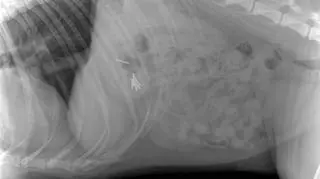

Zdjęcie RTG brzucha psa

Źródło: Uniwersyteckie Centrum Medycyny Weterynaryjnej

Na początku tygodnia ofiarą kiełbasek padła Najra. Pies przebywał na ogrodzonej działce, kiedy najadł się gwoździ. Natychmiast został przewieziony do kliniki weterynaryjnej, gdzie zrobiono mu zdjęcie RTG jamy brzusznej. Jak się okazało, Najra miała w sobie siedem gwoździ. Konieczna była operacja.